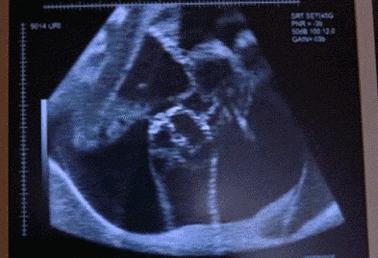

据台媒报道,台湾一名怀孕35周的产妇,在胎儿一阵狂踢后觉得腹部剧烈疼痛,超音波显示出现前置胎盘及羊水减少的现象,医院立即对该孕妇进行剖腹产。

在准备逢合子宫前,医生发现产妇子宫左上脚破了一个近8厘米的大洞,负责治疗的医生称该名产妇出现罕见的产科并发症:产前子宫破裂。原来,小女婴在妈妈子宫里练“武术”,导致妈妈的子宫被踢出一个洞,不但羊水漏光,还不断出血。

看看调皮的宝宝到底在肚子里有多闹腾?